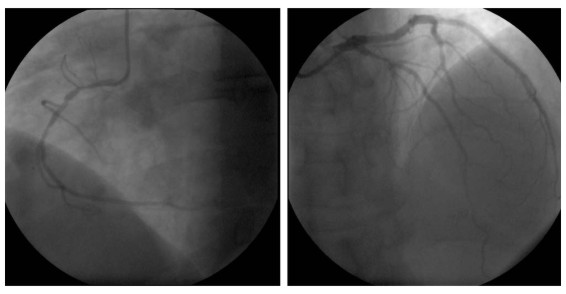

Figura 5. Cineangiocoronariografía

INFORME

Arteria coronaria derecha (ACD): dominante. En tercio proximal se aprecia una estenosis circunscripta de 70-80%. Tercio medio con irregularidades parietales que no constituyen lesiones estenosantes severas (50%).

Arteria coronaria izquierda (ACI): tronco principal: no tiene evidencia de lesiones.

Descendente anterior: en el tercio proximal, en la zona de emergencia del primer ramo septal y la primera rama diagonal observamos una lesión extensa de grado significativo (80%-90%). El lecho distal de buena extensión, sin lesiones estenosantes a señalar.

Circunfleja: muestra una disminución moderada de calibre (40%-50%) en el tercio proximal. No hay otras lesiones de destaque. Ramo marginal obtuso de buen desarrollo, libre de lesiones estenosantes a señalar.

Una vez concluido el estudio se optó por efectuar angioplastia percutánea transluminal para tratar las lesiones proximales de la arteria descendente anterior y de coronaria derecha.

La estenosis proximal de la arteria descendente anterior fue dilatada por medio de un catéter balón Sprinter de 2.5 x 15 mm. A continuación se implantó un stent liberador de Everolimus Abbot Xience V 3.0 x 23 mm desplegado con 16 atmósferas. Se alcanzó muy buen resultado angiográfico.

Acto seguido se abordó la arteria coronaria derecha. La estenosis proximal de esta arteria requirió el implante de un stent Medtronic Driver 3.0 x 15 mm desplegado con 16 atmósferas. Nuevamente se alcanzó buen resultado angiográfico y el procedimiento se completó sin incidentes adversos. El paciente evolucionó de manera satisfactoria hasta el momento del alta.